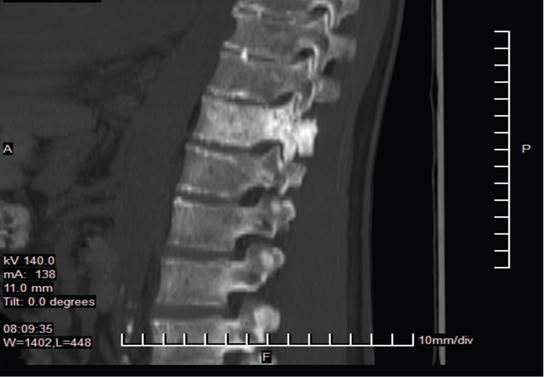

Estudios de orina revelaron hematuria con 28-30 eritrocitos por campo y bacterias escasas de etiología Klebsiella spp. Se realizó Tomografía Axial Computarizada (TAC) de abdomen y pelvis, mostrando enfermedad diverticular, y Resonancia Magnética (RMN) de columna que evidenció lesión tumoral sólida en T11, con compresión del cordón medular (ver imágenes 1 y 2) y adenomegalias en T9 y T10. Además, se detectaron hemorroides grado I y osteoporosis con desmineralización del 39%.

Figura 2: Detalle de infiltración metastásica en T11 (Corte sagital - Resonancia Magnética) Vista ampliada de resonancia magnética sagital que enfoca el cuerpo vertebral de T11, revelando una infiltración metastásica. Autoría: Clínica del Valle